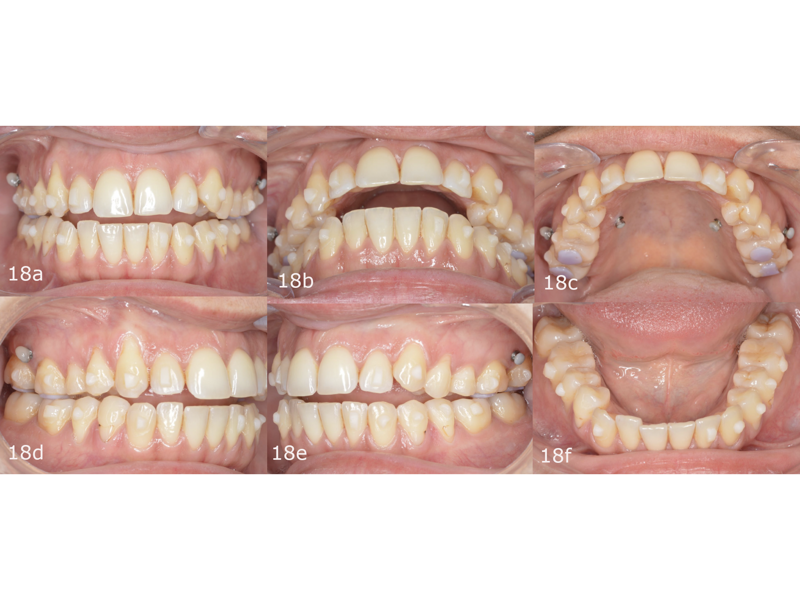

Initial treatment in 29 stages was planned, by which point the final occlusal results would have been obtained. We began with the placement of attachments and micro-screws in the maxillary arch for posterior intrusion (Fig. 18). After seven months of treatment and in the 20th stage, we introduced the FAS STOP and GO concept and took new records to prepare for the second phase of aligner treatment (Fig. 19). Thanks to STOP and GO, it is possible to achieve better tracking so that aligners fit properly and shorter treatment times using fewer aligners. This is the advantage of planning in different stages. It helps us achieve all our treatment goals on a consistent basis, and treatment efficiency is much higher.

The second phase of treatment began with the placement of new attachments (Figs. 20–22) and consisted of 12 stages, during which we continued to intrude the maxillary molars, centre the mandibular midline and level the occlusal planes. This phase lasted for four months. The total treatment involved 32 stages over 11 months, and all the treatment goals were achieved (Figs. 23–25).